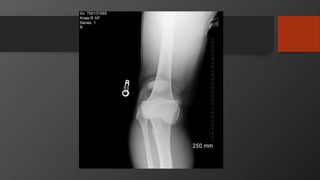

• Imaging

• X-Ray: AP, Lateral

• MRI for surgical planning (later)